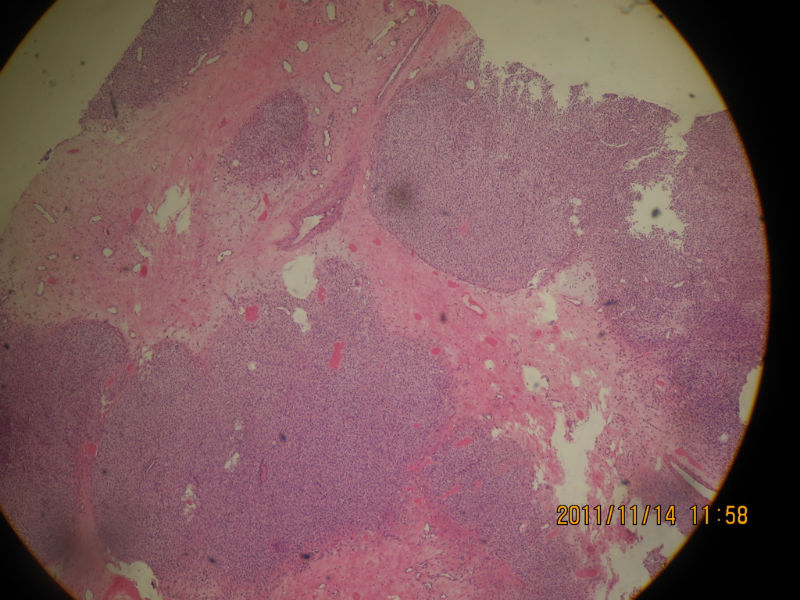

女性 65岁 鼻腔肿物

粘膜下肿瘤,瘤细胞大小一致,无异型性,符合涎腺型肿瘤。

肿瘤位于粘膜下,呈叶状,间隔可见血管组织,瘤细胞圆形,较为一致。瘤细胞周围可见典型的神经纤维基质(最后一图)。考虑嗅母。最好再加做CD99、NF、GFAP、Syn、Ki67。

免疫组化结果:

SMA(+),DES(-),CD34(-),S100(-),CK(-),VIM(+),HMB45(-)

,NSE(-),CD3(-),CD20(-)

结合免疫组化结果,符合血管球瘤

弥漫成片的小圆细胞,大小一致,界限较清,胞浆透亮,可见不明显的血管增生,首先考虑血管球瘤,需要做免疫组化鉴别(SMA,Caldesmon,DES,CD34,S100,CK,VIM)。血管球瘤主要发生于肢体远端的动静脉吻合支,偶可发生于血管球结构稀疏或缺如的部位,据报道,身体很多部位都可发生。